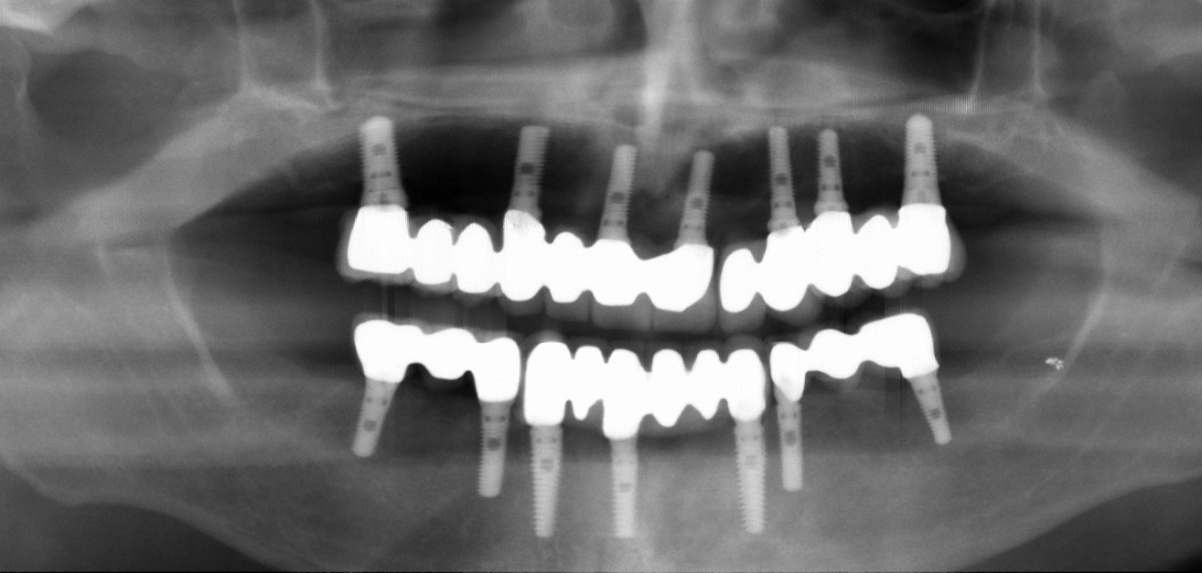

Traditionally, an implant placed into your bone supports a single crown and this is know as a "single tooth implant". However, if you have several missing teeth, you do not necessarily need an implant for every missing tooth: one implant can support several teeth via a bridge or denture. The number of implants required depends on the volume and density of bone tissue available at each implant site.

In the case of full-mouth reconstructions, where an arch of several teeth needs to be supported in either the upper or lower jaw, a minimum of 4 to maximum of 8 implants in each jaw would be required.